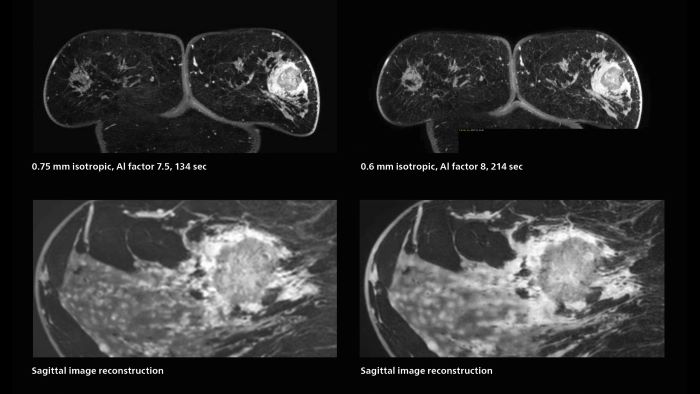

Speed and high image quality are also important factors determining the diagnostic value of breast MRI. “When the spatial resolution is not high enough for making the diagnosis of breast cancer, a very difficult decision must be made,” says Dr. Katahira. “Since SmartSpeed now allows us to increase the resolution, we can often easily provide a confident answer. In the past with SENSE we used 1.2 mm isotropic voxels in breast imaging after contrast admission. With Compressed SENSE that is 0.8 mm. Now with SmartSpeed we can acquire 0.6 mm isotropic voxels and the images are so clear that even tiny details are clearly visible.” “For example, we can now scan 20 consecutive, very fast dynamic images of the mammary glands with a single 3-second volume acquisition. This allows us to see how the blood flow is progressing in a very different way.” “The use of SmartSpeed has considerably improved our breast cancer imaging, with higher temporal resolution, higher spatial resolution, and higher SNR compared to the past, when we were using just Compressed SENSE. In addition, the dynamic study is now more useful in diagnosis because the ultrafast dynamic scan can be taken every 3 seconds.”

Scanning was performed with two different voxel sizes. AI enabled volume MRI allows image reconstruction in other directions. Biopsy revealed invasive ductal carcinoma in this patient. Performed on Elition X.